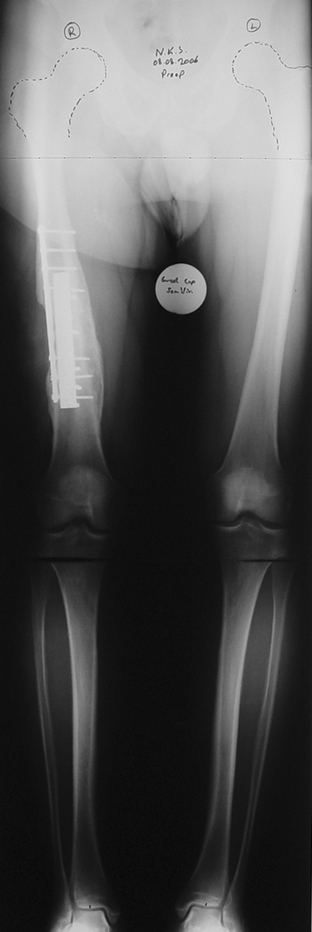

Appropriate radical debridement necessitates excision of all necrotic bone and soft tissues, and frequently causes instability at the involved extremity. The remaining bone and soft tissue defect has to be fixed and reconstructed. The distraction osteogenesis method of Ilizarov is used successfully for achievement of union, correction of the deformity, elimination of limb length inequality and reconstruction of segmental bone defects.

The duration of external fixation (external fixation index) depends on the amount of distraction required, and the extremity is prone to complications during this period. After the distraction phase is completed, the external fixator remains in place during the consolidation phase, which lasts twice as long as the distraction phase; but this period is hardly tolerated. If the external fixator is removed before sufficient consolidation is achieved, fractures, deformity and shortness will be the result. In our department, ‘lenghthening over nail’ method is used in order to decrease the external fixation index and increase patient comfort and activity level. In this method, the intramedullary nail is statically locked after the completion of the distraction phase, and external fixator is removed. The extremity is stabilized by the intramedullary nail during consolidation phase. In this way, complications due to long external fixation index or early removal of the external fixator are avoided.

Case 1